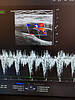

Так, одна из пациенток поликлиники №2 на протяжении многих лет наблюдалась у кардиолога из-за гипертонической болезни, ожирения и сахарного диабета 2 типа. Ей была успешно проведена радиочастотная абляция рецидивирующей формы фибрилляций предсердий. Через какое-то время у женщины появились новые симптомы – варикозное расширение вен и боли в правой голени. Врач-хирург направил пациентку на допплеровское исследование артерий и вен нижних конечностей.

Ирина Ковальчук сумела выявить причину неприятных симптомов. Оказалось, что у женщины образовалась артерио-венозная фистула – аномальное соединение между артерией и веной, которое нарушает кровообращение, может привести к образованию тромбов и сердечной недостаточности.

– Благодаря своевременному выявлению фистулы пациентка была направлена к ангиохирургу. Диагноз был подтвержден, назначено лечение, – подчеркнула заведующая отделением функциональной и ультразвуковой диагностики. – Пациентка находится на диспансерном наблюдении и чувствует себя удовлетворительно. Врачи отмечают положительную динамику: размеры артерио-венозной фистулы уменьшились, что улучшило прогноз заболевания.

фистула 1